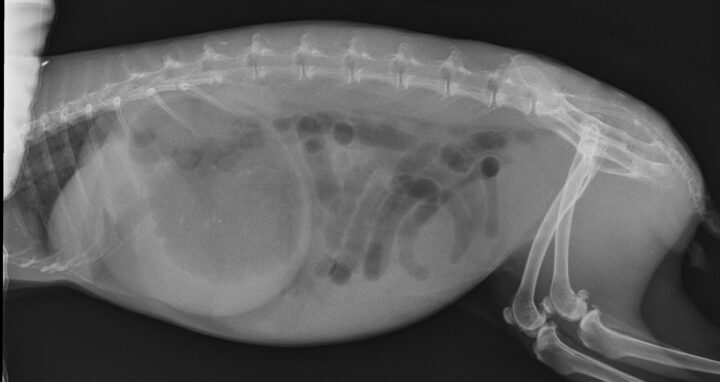

Gastrointestinal obstruction in rabbits is not uncommon, and it is imperative that clinicians are able to differentiate cases of obstruction from cases of gastrointestinal stasis. It is important that obstruction cases are identified early, as intensive treatment must be started swiftly. As rabbits cannot vomit, gastrointestinal contents proximal to the obstruction continue to build, and gas accumulates as the contents ferment, resulting in severe intestinal and gastric tympany; in prolonged cases, this can lead to rupture of the gastrointestinal tract (Figure 1).

Cases of obstruction were more likely to have gastric distension where the sum of the height and length of the stomach was greater than or equal to the length from the first lumbar vertebra to the coxofemoral joint. Ninety-two percent of obstruction cases showed contact between the ventral aspect of the stomach and the ventral abdominal wall. In addition, most obstruction cases showed gastric contents consisting primarily of liquid with a “gas cap” (Figure 3A), whereas gastrointestinal stasis cases showed evidence of normal stomach ingesta (Figure 3B).

In cases of obstruction, gas in the small intestine but absent in the caecum is also a common finding (Huynh and Pignon, 2013).